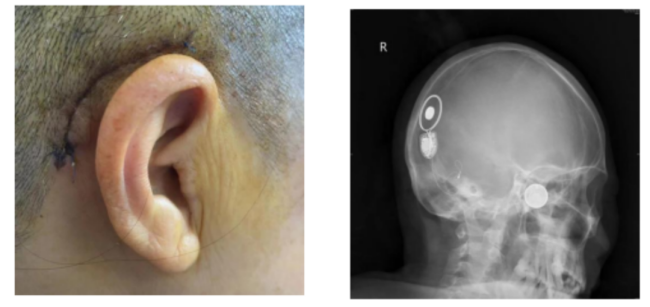

李女士接受人工耳蜗植入术后的影像图片

(南华大学附属长沙中心医院)耳鼻咽喉头颈外科专家团队为李女士进行了右侧人工耳蜗植入手术。术中,手术团队对植入的电极进行了电极阻抗测试和神经反应遥测(NRT),均提示人工耳蜗电极工作良好,电阻正常,神经反应良好,手术顺利完成。如今术后1个月过去了,植入的人工耳蜗开机调试,李女士对声音反应好,连连感谢专家团队实施手术和精心护理,让她能清晰听见这个世界的声音。